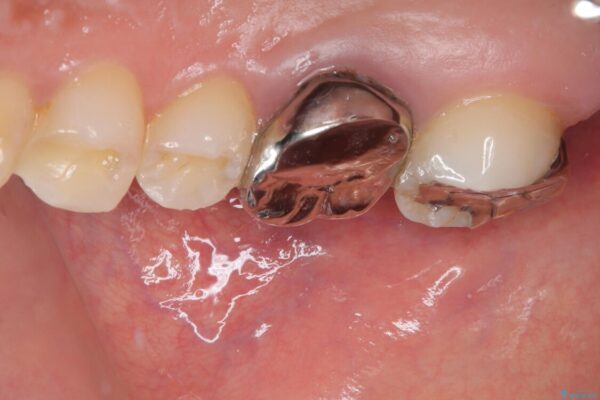

しかし、噛み合わせの相手である右上の第二大臼歯が、長期間噛み合う歯がなかった影響で**挺出(歯が下に伸びてくる状態)してしまっており、このままではインプラントを埋入して被せもの(上部構造)を入れるためのスペースが不足している状態でした。

そこで、右上の奥歯に部分的なワイヤーを装着し、さらに矯正用アンカースクリュー(TADs)を併用することで、挺出した歯を圧下(歯を元の高さに戻す動き)させ、下顎にインプラントを埋入するための十分な垂直的スペースを確保しました。

治療途中

• 挺出歯を圧下してスペースを確保!目立たない部分矯正で下顎大臼歯にインプラント治療を実現 治療途中画像